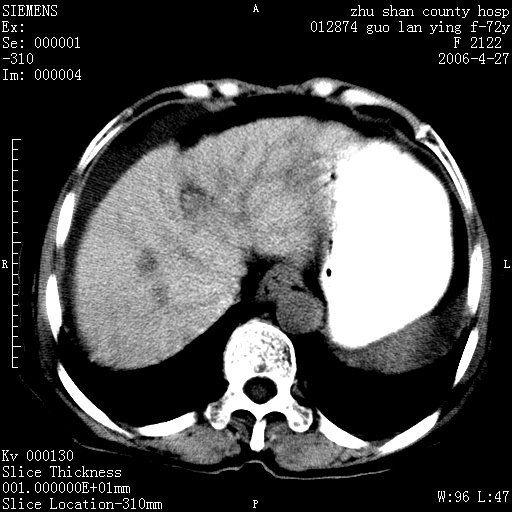

病人 女性 72岁 b超要求ct检查!

平扫所见:胆囊区两点壮高密度影,灶周有伪影{请问楼主患者有手术病史?}。肝实质内未见明显异常{建议强化或mri}.腹腔有少量积液,脾明显增大.右肾形态似不规则?

腹腔内示积液征,脾脏略增大,肝脏由于运动伪影较多,影响观察,内未见明显高密度区,胆囊内示两处高密度结石。胃窦部壁轻度增厚。另外,肝脏的前缘似有游历气体。不知病人的临床如何?有必要做胃的检查,还有,看看骨窗是否有腹腔游离气体还是肠管影响的。

肝脏缩小,脾脏增大,肝脾外缘及胆囊窝液性密度影,肝脾ct值正常,胆囊区见两个类圆形高密度影,下腔静脉前方类圆形软组织密度影为肝脏岛叶,胃幽门区见软组织密度影,十二指肠钡剂充盈不好.

1:腹水2:胆囊结石3肝硬化?(不确定,请结合临床)4幽门区占位?(建议胃肠透视)

肝硬化,脾大,少量腹水

肝硬化、腹水、脾大,胆囊结石可以肯定。只是肝右叶两个低密度有必要增强确定一下;排除小肝癌。

谢谢牟教授在百忙之中还认真的点评我的帖子!也谢谢大家的鼎力相助,此病人是我们医院护理部主任的母亲!病人以前无特别不舒适!昨天b超后发现有问题!做ct的目的在于排除肝内占位性病变,此病人以前无手术外伤史.